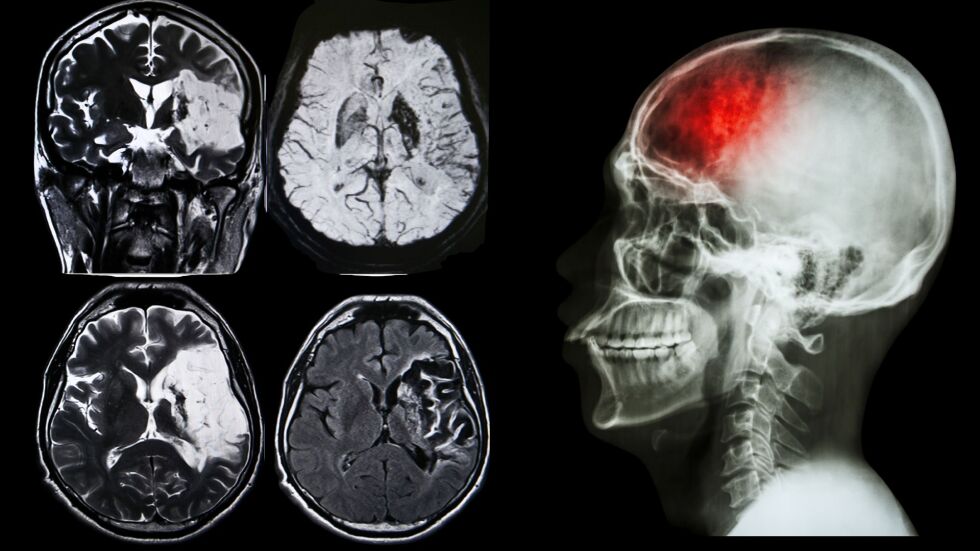

Основателят на БДИ доц. Росен Калпачки представи обнадеждаващи данни за развитието на лечението на инсулт в страната. Въпреки че на фона на европейската цел от 15% постигнатите 4% може да изглеждат скромно, той подчертава, че напредъка е съществено.

За десетилетието от 2014 до 2024 г. броят на тромболизите в България се е увеличил драматично, от 270 годишно на близо 2000, представлявайки 7-8-кратен ръст. Тромболизата е ключова част от съвременното лечение на исхемичния инсулт и постепенно се налага като стандарт във все повече медицински центрове.

Ситуацията с тромбектомията е още по-тревожна - едва 0,3% от исхемичните инсулти се лекуват по този начин, въпреки че това е важна алтернатива за определени случаи.

България заема третото място по заболеваемост и смъртност от мозъчен инсулт в Европа, което подчертава сериозността на проблема в национален мащаб.